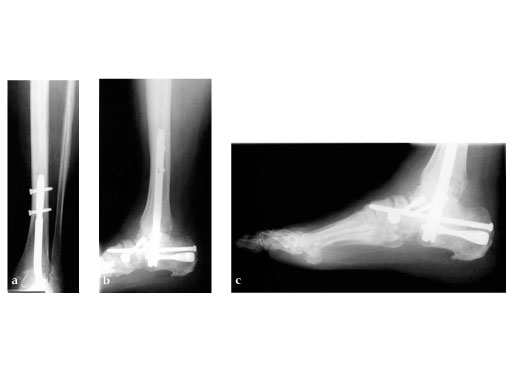

A 64-year-old man presented with severe ankle and subtalar arthritis accompanied by large cysts in the talus and calcaneus. Eighteen months after hindfoot fusion with the HAN he walked without pain.

Case provided by Stefan Rammelt, Dresden, Germany